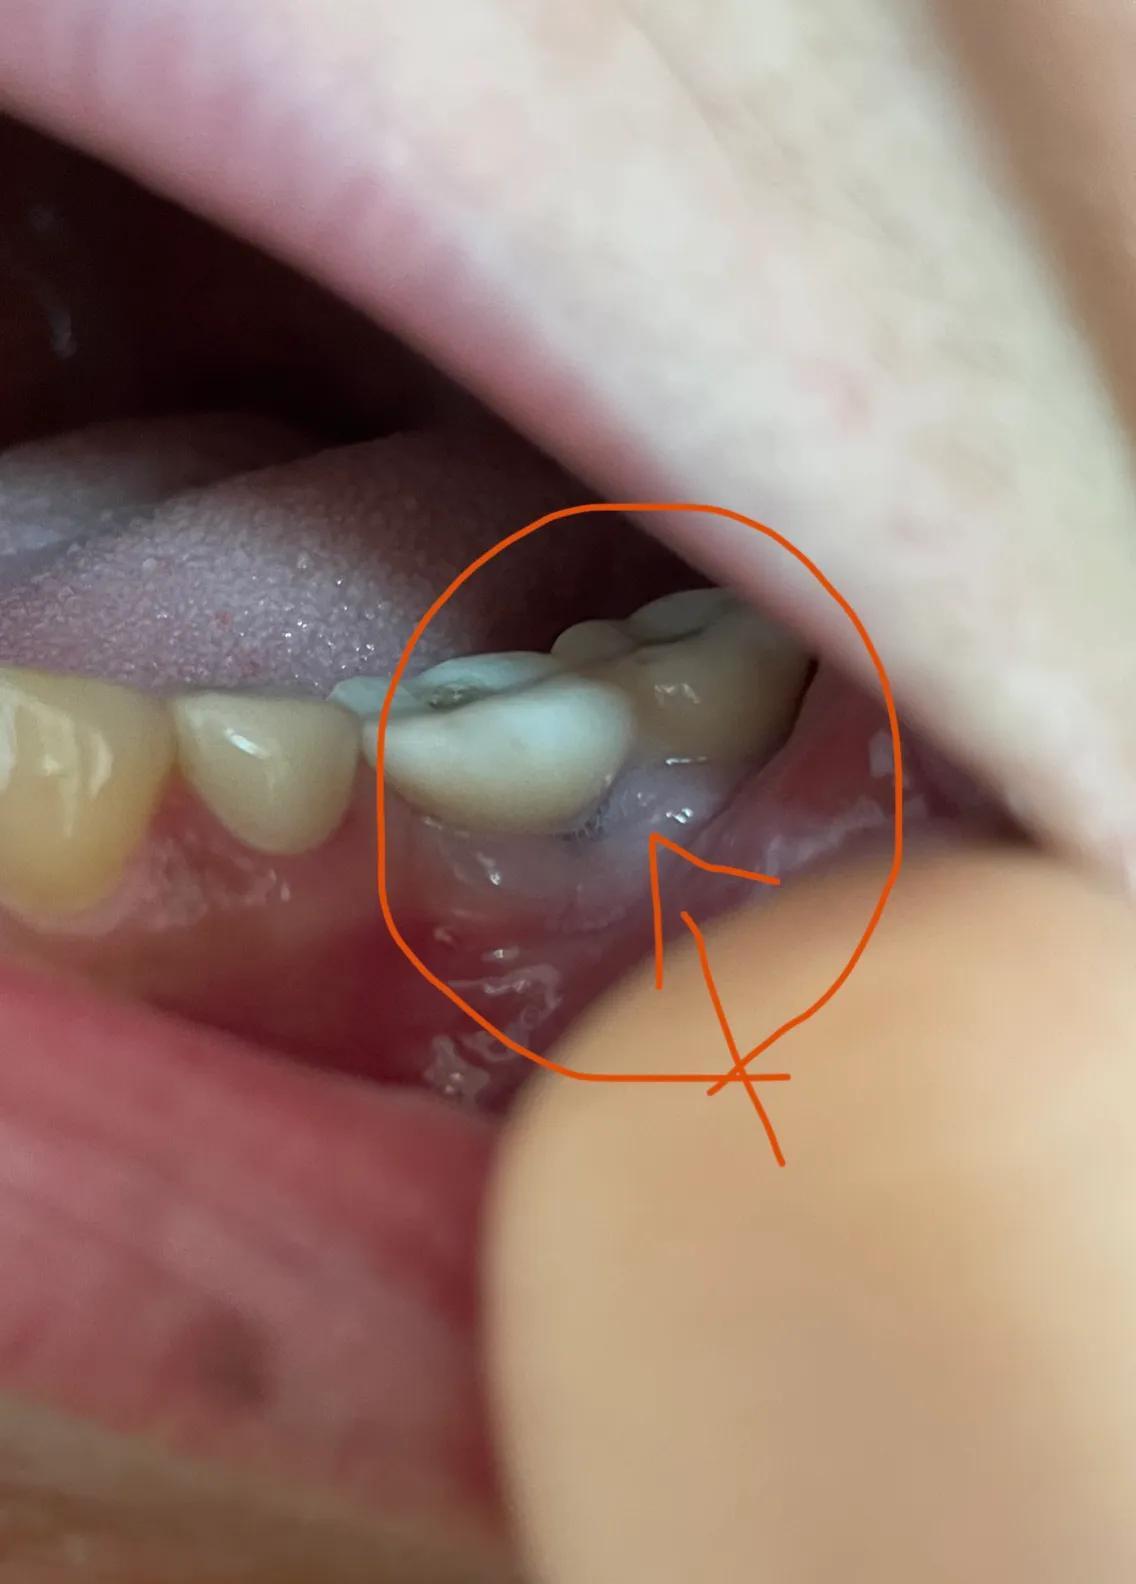

第二副牙帶好 發(fā)現(xiàn)牙齦又缺肉了 更別提貼合牙齒了 而且是一直的疼 一直難受

牙齦是外翻和牙齒分開(kāi)的 顏色發(fā)白 和其他部位牙齦不是一樣顏色

我不是專(zhuān)業(yè)醫(yī)生 不懂他們所說(shuō)的正常現(xiàn)象都包括什么 要怎么后期維護(hù) 我現(xiàn)在先不講看不見(jiàn)的難受 疼 先講直觀能看見(jiàn)的 他們哪位醫(yī)生可以做到把大米粒塞到牙齒下面 和將近半厘米的塑料條塞過(guò)他們的牙齒 吃過(guò)東西就要用沖牙器 不然隔頓就臭了

沒(méi)辦法自己又出去拍片子 找原因 看了幾家醫(yī)院 才知道連種植體也種偏了 牙冠也沒(méi)有就位………